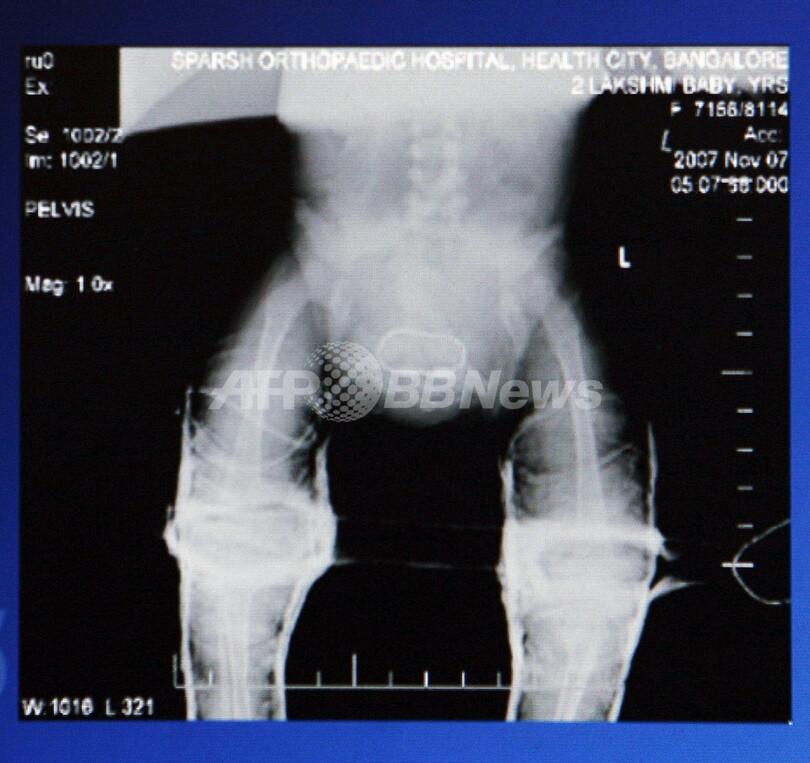

この種のものとしてインド初の手術は、バンガロール(Bangalore)のSparsh病院で行われ、小児科や整形外科の専門医で構成する36人の医師団が執刀。余分な手足を切除して腎臓のうちの1つを残し、骨盤を再生した。